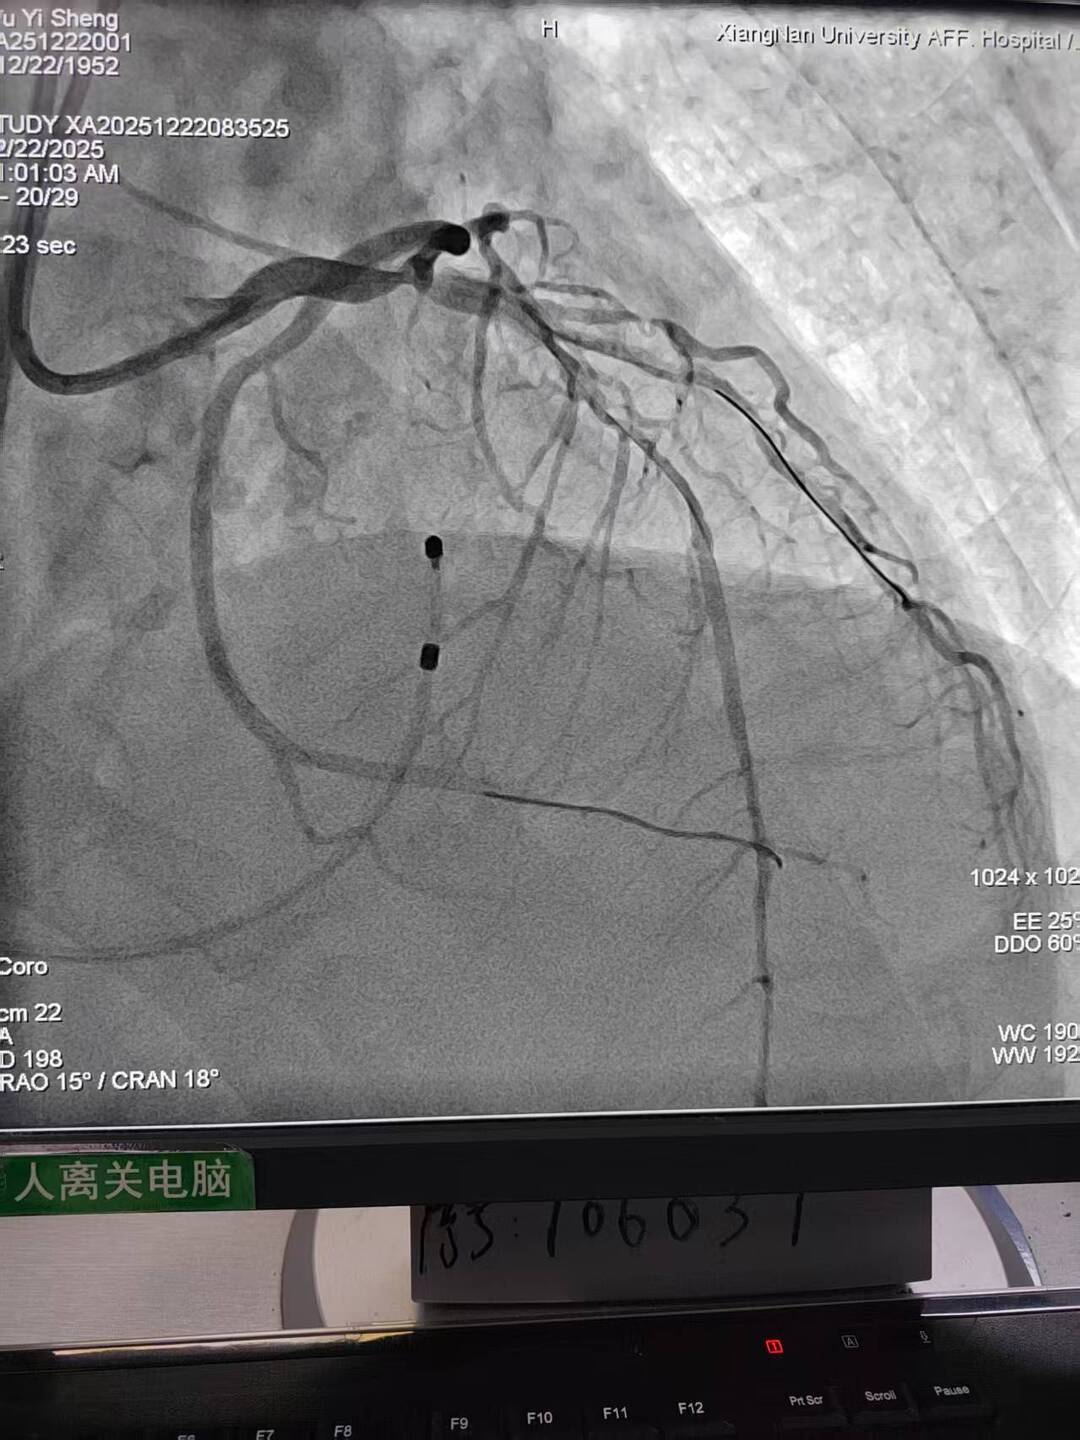

73岁的李先生因反复胸痛、气促入院,活动能力明显受限。经全面检查发现,其冠状动脉主干及多支血管存在多处严重狭窄,心肌供血严重不足;被称为“心脏大门”的主动脉瓣重度钙化、狭窄,已引发心功能衰竭;而外周血管同样存在严重钙化、溃疡与狭窄。这三种病变单独存在均足以危及生命,叠加后使传统外科开胸手术风险陡增,患者一度面临治疗困境。

手术过程犹如在心脏内进行的“微雕”和“换门”工程,步骤环环相扣,每一步都考验着术者的技术功底与团队协作默契。术中,团队首先利用先进的可扩张血管鞘,在严重钙化狭窄的右侧股动脉腔内成功建立安全的手术通路;随后经该微创入路,先通过球囊扩张术为冠状动脉植入支架,快速恢复心肌血供;紧接着,在同一手术台、同一入路下,精准将人工主动脉瓣输送至病变位置并成功释放,顺利替换失灵的原生瓣膜。整个过程中,团队成功克服了外周血管入路困难的核心挑战,确保手术各环节无缝衔接、精准落地。